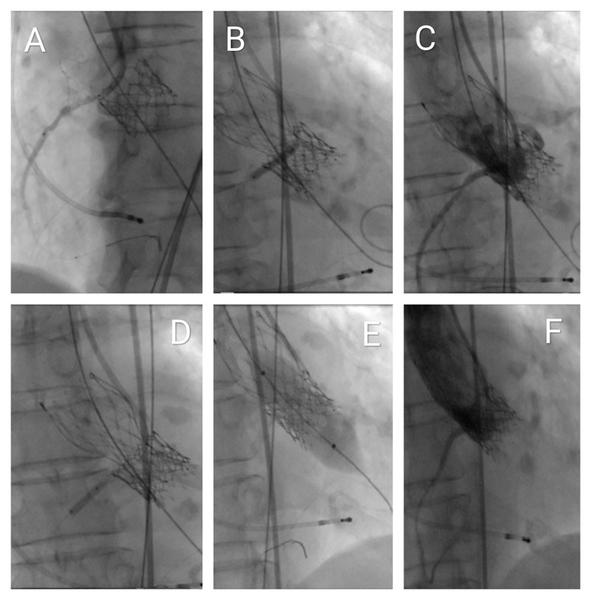

A multipurpose guiding catheter was advanced into the right coronary artery (RCA) ostium, and a Hi-Torque BMW Universal II coronary guidewire was positioned distally. A 2.75 mm × 23 mm drug-eluting stent was pre-positioned with approximately 1 cm protruding into the aorta as a prophylactic measure for bailout coronary protection using the chimney stenting technique. A shorter stent was selected due to suboptimal backup support (Figures 5A, Video 1). The degenerated bioprosthesis was crossed using a straight Terumo guidewire, followed by advancement of an Innowi wire over the pigtail catheter. A 23-mm Evolut FX+ valve was successfully implanted without prior balloon valvuloplasty. Post-deployment, incomplete valve expansion was noted, accompanied by ST-segment elevation in the lateral ECG leads, indicative of impaired coronary perfusion.

Simultaneous percutaneous transluminal coronary angioplasty (PTCA) of the RCA was then performed, deploying the pre-positioned stent using the chimney technique (Figures 5B, Video 2). This intervention resulted in resolution of the ST-segment changes and hemodynamic stabilization. Subsequent angiography revealed a distal RCA stenosis beyond the initially placed stent, which was successfully treated with a second drug-eluting stent measuring 2.5 mm × 12 mm (Figures 5C and 5D, Video 3).

Following the initial deployment of the TAVI prosthesis, hemodynamic assessment demonstrated a peak-to-peak transvalvular gradient of 30 mmHg, indicating the need for further optimization. A stent balloon from the prior percutaneous coronary intervention was retrieved and positioned at the coronary ostium. Subsequent post-dilatation of the valve was performed using a 20-mm SIMVALVE balloon (Figure 5E, Video 4).

During post-dilatation, no ECG changes or deterioration of the previously implanted stent were observed. Therefore, the kissing balloon technique was not performed. Final angiography confirmed Thrombolysis in Myocardial Infarction (TIMI) grade III flow and demonstrated no evidence of paravalvular leak or transvalvular regurgitation. Perfusion of the right coronary artery (RCA) was preserved and appeared satisfactory (Figures 5F, Video 5).

Figure 5. Fluoroscopic visualisation of the interventional procedure

(A) Advancement of the Innowi 35SX wire and positioning of the drug-eluting stent at the ostium of the right coronary artery (RCA), with slight protrusion into the aorta.

(B) Incomplete expansion of the Evolut FX+ valve during implantation and simultaneous PTCA of the RCA for inferior ST-segment elevation.

(C) Coronary angiography of the RCA showing stenosis distal to the first stent.

(D) PTCA performed on the distal RCA lesion beyond the initial stent.

(E) Post-dilatation of the valve using a 20-mm SIMVALVE balloon.

(F) Final aortography via pigtail catheter showing good RCA flow with no valve regurgitation or paravalvular leak.